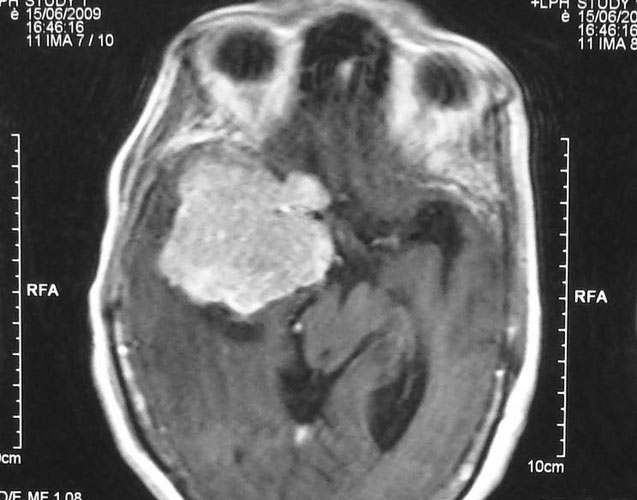

Arteriovenous malformations

Arteriovenous malformations of the brain are abnormal bunch of blood vessels that can rupture causing bleeding, or may cause seizures. Brain imaging (CT, MRI) is required for early diagnosis, while definitive treatment is carried out after cerebral angiography. Treatment implies craniotomy and excision of the AVM, which can be done safely in majority of the cases. Embolisation and radiosurgery are acceptable substitutes, but carry risk of further bleeding.